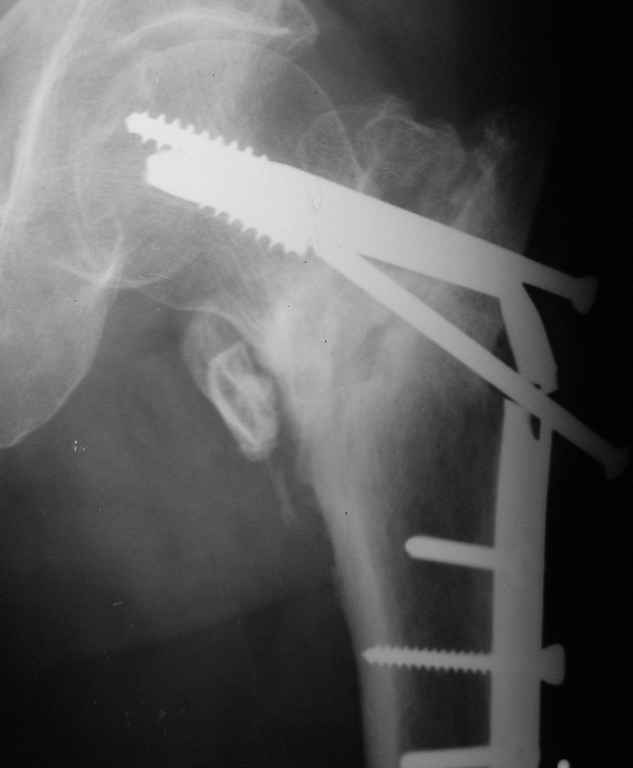

Подскажите пожалуйста, кто как и чем удаляет сломанные спонгиозные винты из шейки и головки бедра.

Имя     : P3192383.jpg